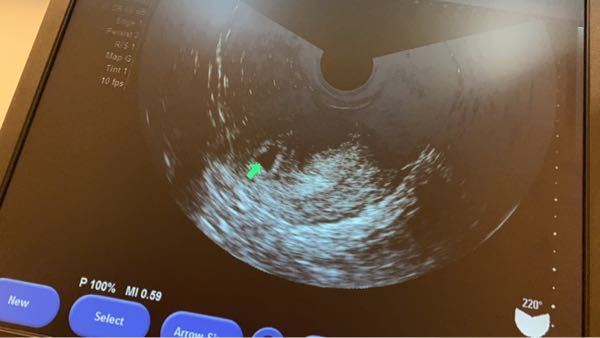

妊娠判定から卒業までの流れ 受精卵を移植された方は、妊娠判定を行い移植後の経過を見ていきます。 ①採血によるホルモン測定 (妊娠反応陽性) ②エコーによる胎嚢確認 (臨床妊娠成立) ③エコーによる胎児心拍の確認 (心拍確認) *妊娠週数について 妊娠 今日で生理予定日から一日経過中です。 排卵日から数えて今日で15日目です。 排卵日は検査済みなので間違いないと思います。 明日病院に行って胎嚢が確認される確率はありますか? 仕事の休みの関 心拍確認を迎えるためにも、まずは胎嚢確認を無事迎えるようにしてください。 関連記事 胎嚢の確認はいつから?流産の確率と心掛けたい過ごし方まとめ 胎嚢確認まで気をつけることは冷えと姿勢。

心拍確認 胎嚢が確認出来たら、つぎは赤ちゃんの 心拍確認 です。 心拍は妊娠6週~妊娠7週ごろ確認できることが多い ようです。 私は医師から(胎嚢確認の)2週間後に再診するように言われました。 妊娠7週3日の診察で、ドクドクととても早い赤ちゃん 妊娠をハッキリ確認できるのは、6週以降がいいと思います。 私も5週で行ったことがありますが、胎嚢は確認できませんでした。 あまり早いと、来週もまたっていわれますし、 自費診療になるので、1度に5000円弱かかりますから、 心拍確認できるのはいつから? 妊娠5〜6週(生理予定日より2週間以上すぎたあたり) になると、ほとんどの場合で赤ちゃんの心拍が確認できます。 この時期は妊娠2ヶ月あたり「妊娠初期」になります。 赤ちゃんの心拍は、基本的に「超音波検査」で